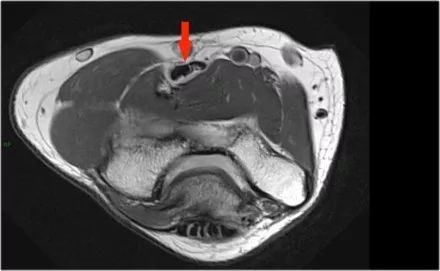

尺神经:在这里,我们看到了肘管内的尺神经。尺骨侧支带的后带形成隧道的底部,而支持带形成屋顶。

该患者有尺神经神经病变。肘管综合征是一种常见的周围神经病变。它产生于肘管内尺神经,其中该神经传递肘管支持带的下方的压缩。

因此,当我们回到图像时,您会发现很难找到神经。任何这些皮下结构都可以是转位神经。一种方法是远端跟随结构,直到你发现远端的尺神经位于由脂肪包围的前臂近端的正常位置。然后当你向近端跟随它时,你会发现这是皮下移位。

在这种情况下,有神经炎。神经增大。在T2W图像上有高信号。另一个标志是在矢状图像(箭头)上看到的束的不均匀扩大。